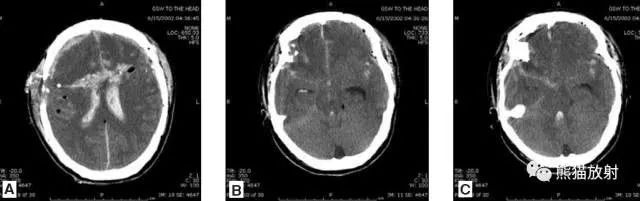

颅脑CT常用的三个窗(图A-C):图A:骨窗(the bone window)。

图B:脑窗(the brain window)。

图C:血窗(the blood window)。

图A:骨窗;主要用于明确骨折、窦腔病变、颅内积气。

图B:脑窗;可清晰显示灰白质,可发现中风的早期征象或其他导致脑水肿等表现的病变。

图C:血窗;更利于显示硬膜下或颅内出血。本例表现:骨窗示:右顶骨骨折;三个窗均示:软组织水肿并皮下积气;血窗:少量硬膜下血肿。